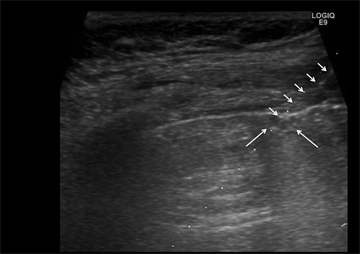

All patients were evaluated using the GE LOGIQ Q9 US imaging system (GE Healthcare Worldwide, Chicago, IL, USA). US examinations were performed by an interventional radiologist (with experience of >30 years). Patients were placed in the supine, prone, or right/left lateral decubitus positions. The indication of fusion image depended on the same interventional radiologist. Initially, US using the conventional B-mode was conducted to identify CT-detected lesions. When a solid nodule was not identified through conventional B-mode, fusion image with real-time US and CT was performed using a commercially available US unit (Figure 1). Moreover, fusion image was successful in localizing the part-solid GGN with pleural involvement, despite non-detection of the ground-glass opacity within the sonographic window (Figure 2). For the fusion image, the manubrium of the sternum served as a reference point to synchronize the spatial relationship between the CT and US images in supine position. In the prone or lateral position, the first or 12th spinous process was used as a reference point. Once

Figure 2. An 80-year-old man with a 20-mm part-solid GGN. (a) Chest CT scan showed a peripheral pulmonary part-solid GGN; (b) Fusion imaging of the contact area between the pleura and the solid component to localization of the lesion; (c) The inserted line was visualized as a dotted line through the contact area between the pleura and the solid component (long arrow). The biopsy needle (short arrows) was introduced into the lesion along the dotted line; subsequently, two samples were obtained without occurrence of pneumothorax. The biopsy revealed that the lesion was adenocarcinoma.